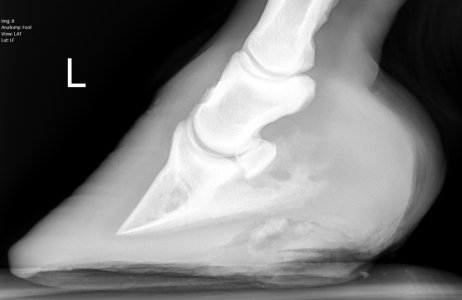

Good that you found out now before you got a huge laminitis episode. This is completely and utterly fixable though, and relatively quickly. Once the inflammation comes down, the rotation will reduce and all will be good. It’s just management changes now - trial and error (we got past the more general vet to the practice specialist eventually and following her advice was the key!). Our Shetland was so so poorly with EMS induced laminitis and yet now you would never know. She’s skinnier than she’s ever been, but so long as we keep her on her strict diet and provide enough exercise, she’s sound as anything, in full work and very happy.

Personally I’d (at least short term) get shoes on him to help address quite clear balance issues. For a variety of reasons, more immediate comfort to assist with better movement (weight loss benefits). Reduce the risk of poor compensatory patterns (potential for soft tissue/arthritic changes).

One alignment is better and you have any weight/metabolic issues under control, by all means aim to remove the shoes.

I’m inclined to agree with ihw re putting shoes on in the short term to correct the imbalances, plus repeat x rays to monitor progress. That is what I did with my homebred with poor front foot balance. The shoes came off again later.